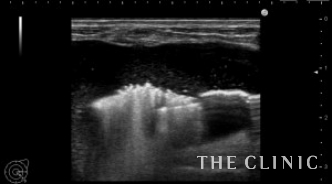

除去したヒアルロン酸です。

ヒアルロン酸注入によるしこりのエコー診断カルテ